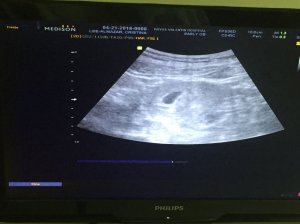

During the first ultrasound sesh, it was confirmed that I was pregnant. I was told that the fetus is in early weeks of development and a followup ultrasound (pelvic ultrasound) is needed for a more accurate look at the fetus. Here’s my little peach as seen using the ultrasound:

The pelvic ultrasound (or trans-vaginal ultrasound) yielded a clearer image of the fetus. The fetus is the tiny white dot you’re seeing in the middle of that black oblong thing called a yolk sac:

Above is a zoomed-in image of my little peach. The cool part? The heartbeat was already detected so early. The doctor said, “Ma’am siguro po maniniwala na kayo na buntis ka kasi may heartbeat na,” (Ma’am, maybe now you’ll believe that you’re pregnant because (the baby) there’s a heartbeat) while zooming in on the white dot. It was so cool seeing the heartbeat, it looked as if the white dot is dancing.